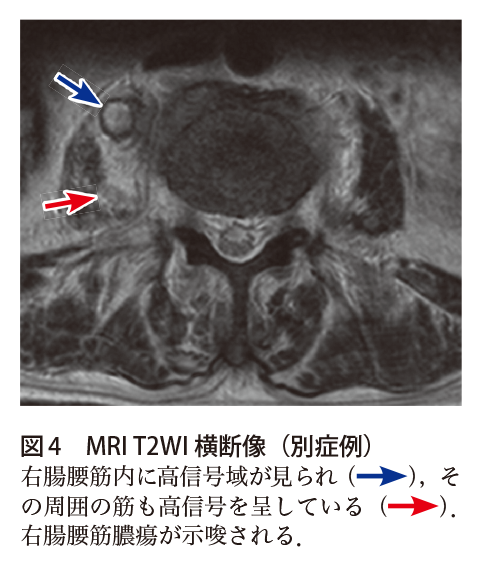

• 腰背部痛の有無(腎梗塞、腸腰筋膿瘍) • 頭痛の有無(sepcemboli) 病歴聴取のポイント Q11!亀田感染症ガイドライン uti以外にも尿道炎、尿路結石、腸腰筋膿瘍などでも認める(utiに対する特異度は低い) が、utiで認めないことはまれ(感度は高い)。膿尿がなければutiでない可能性が高い。腸腰筋膿瘍 ガイドライン 膿尿がなければutiでない可能性が高い。 腸腰筋膿瘍のct、mri画像所見 他の部位の膿瘍と同様に、ctにて内部低吸収を示し、mriでは、t1wiにて低信号、t2wiで高信号を示し、 造影で辺縁に造影効果 を認めるのが特徴。

Gent in Italy because of immigration from Africa and Asia Osteomyelitis requires long and expensive antibiotic treatment, including rifampicin administered parenterally for several weeks and the use of antimicrobialimpregnated cement in prosthesis substitution Sometimes it is necessary to carry out surgical debridement of a necrotic bone or the consolidation of compromised bones 腸腰筋膿瘍のct、mri画像所見 他の部位の膿瘍と同様に、ctにて内部低吸収を示し、mriでは、t1wiにて低信号、t2wiで高信号を示し、 造影で辺縁に造影効果 を認めるのが特徴。 ただし、膿瘍内の蛋白濃度が高い症例では、t1wiで高信号を示すことがある。左葉に生じた特発性の多房性、多発性肝膿瘍は 穿刺吸引では治療効果は乏しく、外科的治療が必要 巨大な膿瘍、特に多房性や粘度の高い膿汁の場合、 278%で経皮的持続ドレナージが功を奏さない Sommariva A et al, Eur J Gastroenterol Hepatol 06;